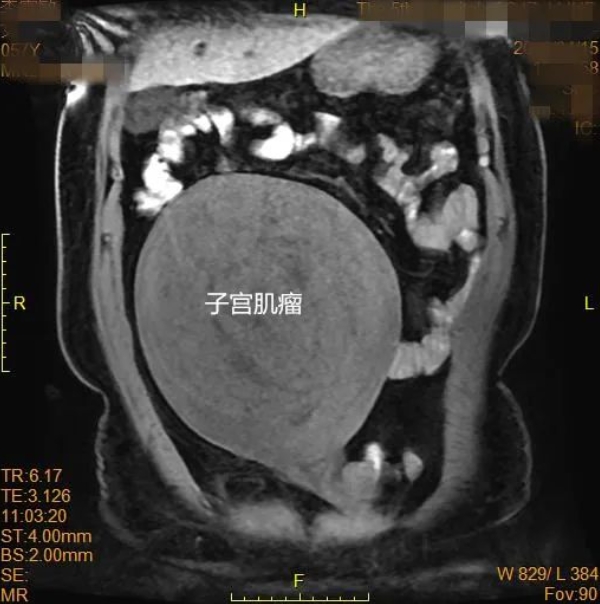

妇产科主任赵玉婵为患者进行了详细检查,患者子宫肌瘤直径超过22cm,占据整个盆腔并压迫多脏器,手术难度极大,若不及时切除,随时可能引发大出血或器官衰竭。面对患者强烈的治疗意愿,“尽早安排手术!”赵玉婵主任本着对患者高度负责的态度果断发出指令。她带领团队医护人员迎难而上,迅速组织会诊,制定了周密的手术方案和应急预案。

经过充分的术前准备,手术如期进行。术中可见肌瘤与周围血管、肠道及膀胱紧密粘连,稍有不慎即可能引发大出血或损伤。赵玉婵带领医护团队,凭借丰富的经验和娴熟的技术,精准剥离肿瘤,成功止血,同时完整保留了患者的子宫。手术历时3小时,重达6斤多的肌瘤被成功切除,术中出血量仅300ml,远低于预期,手术圆满顺利!